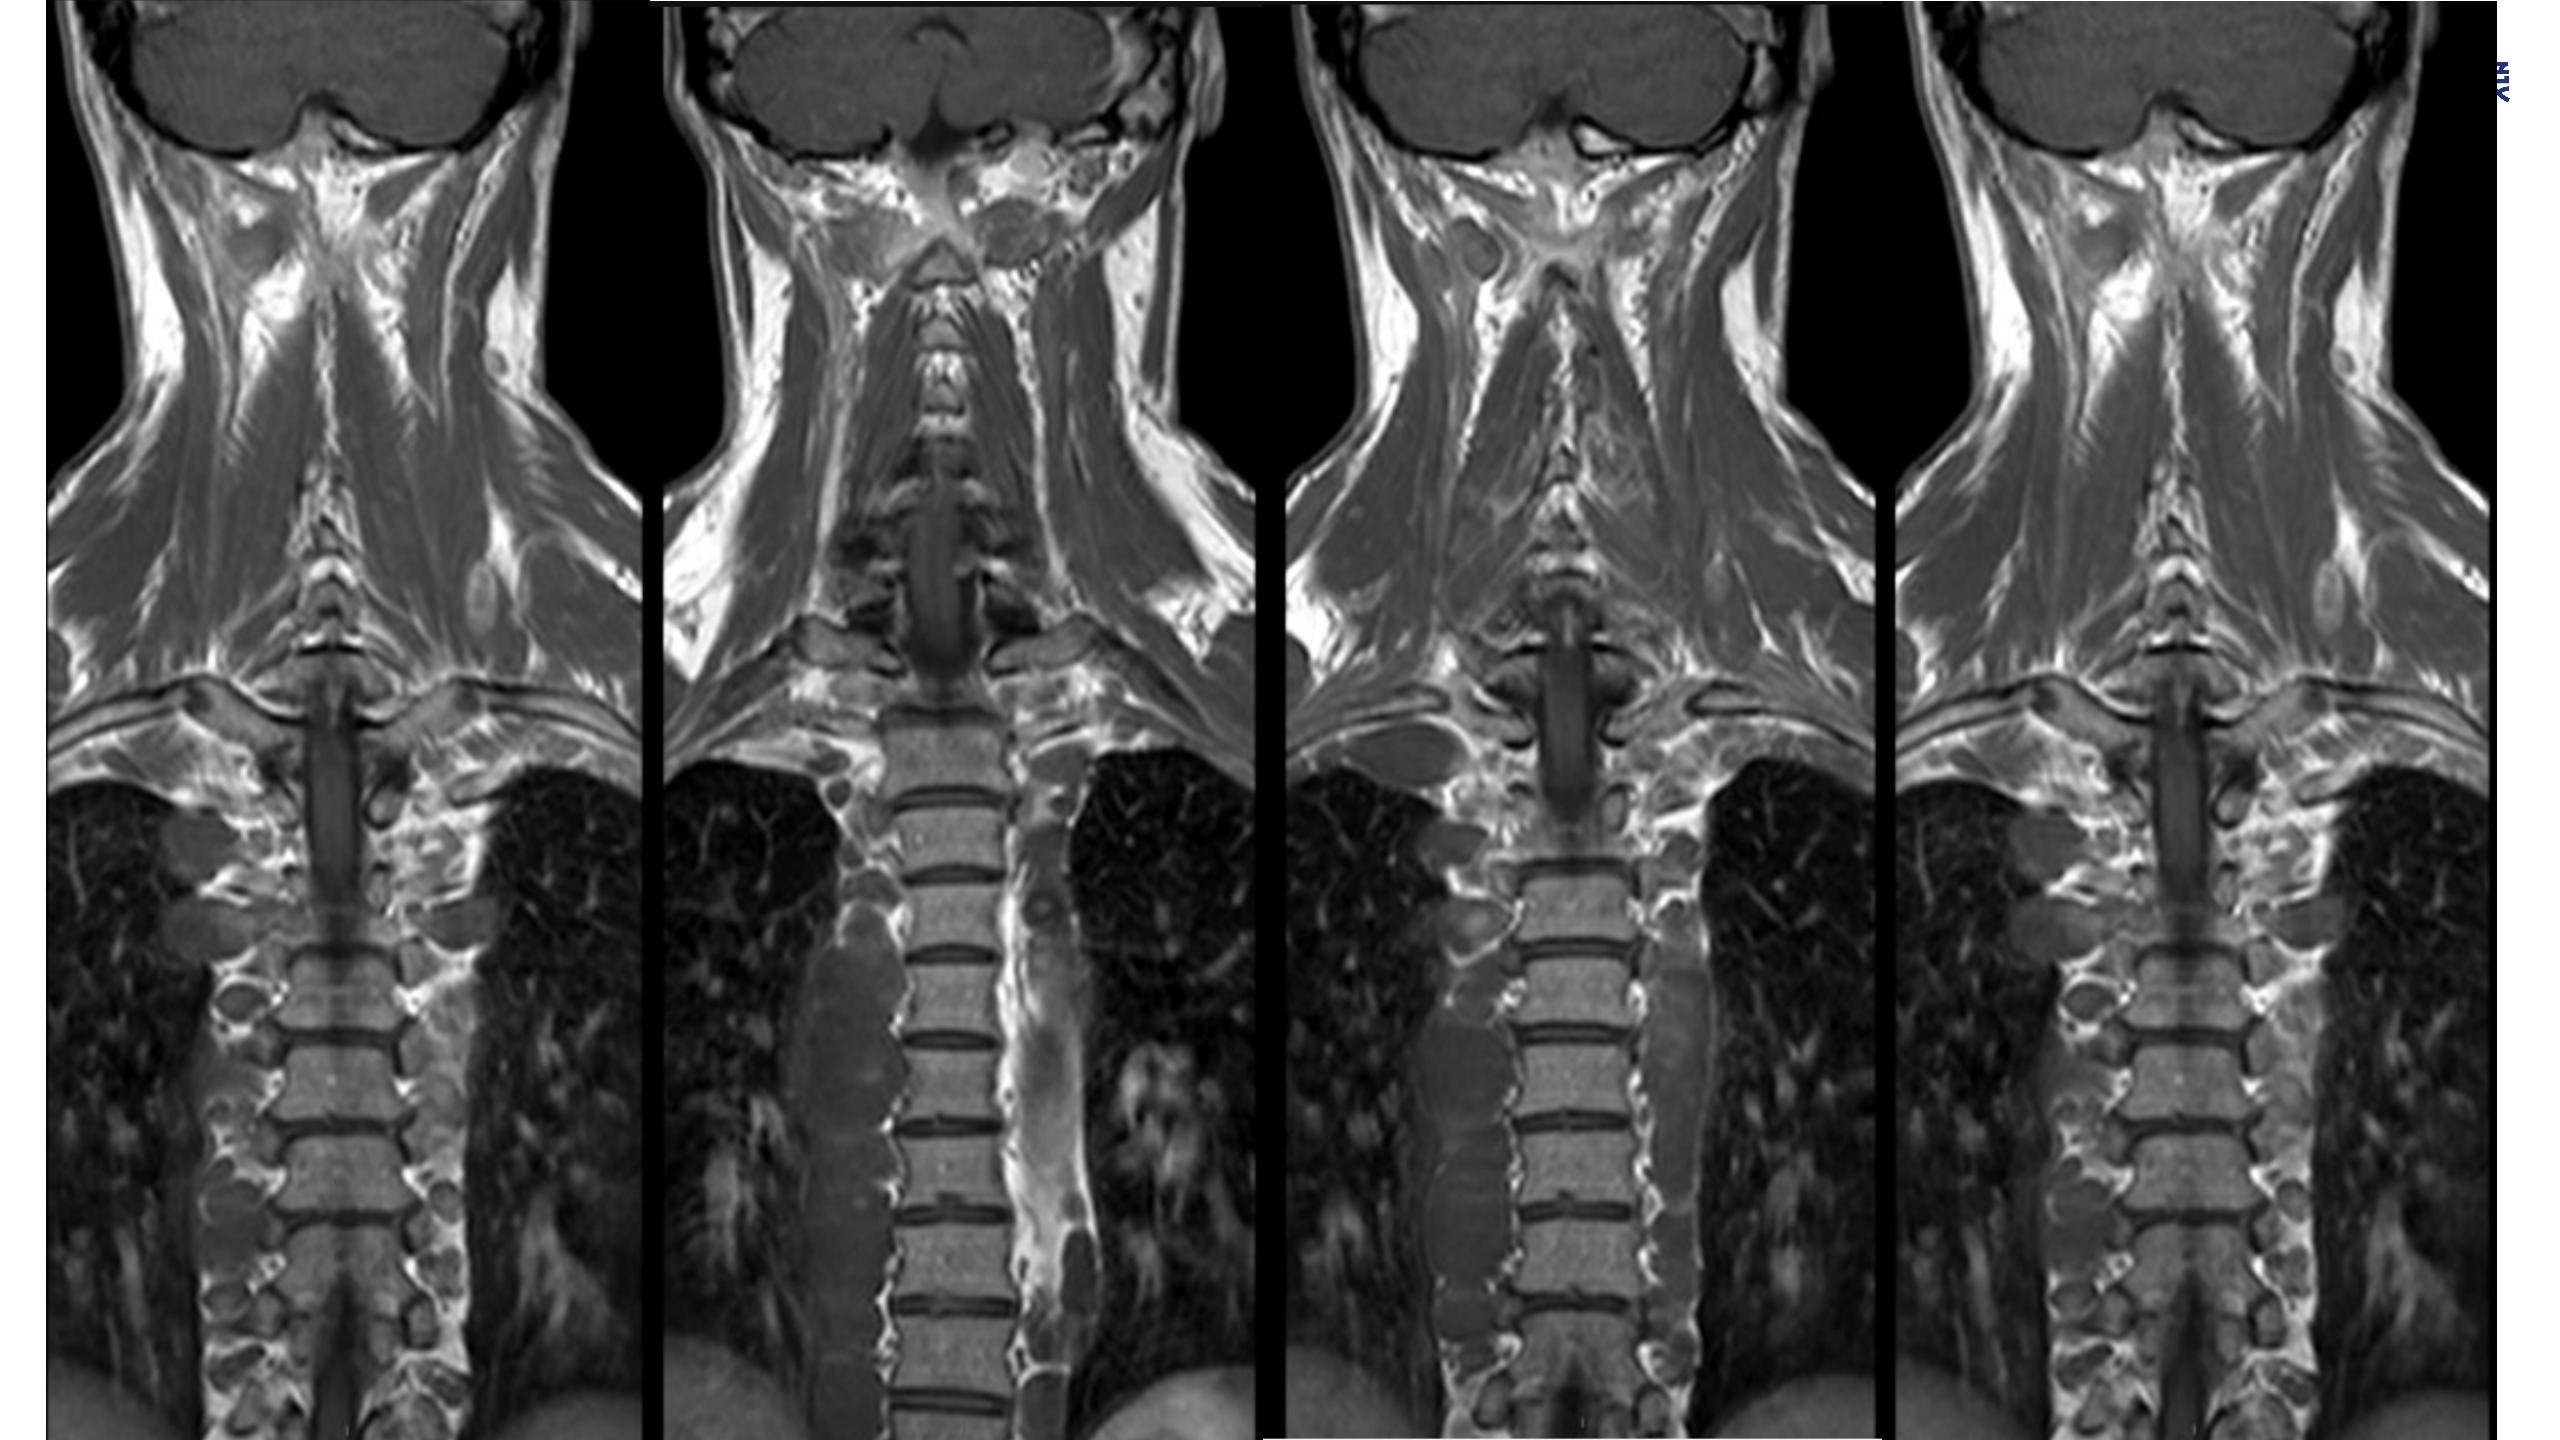

神经纤维瘤病(NF1)